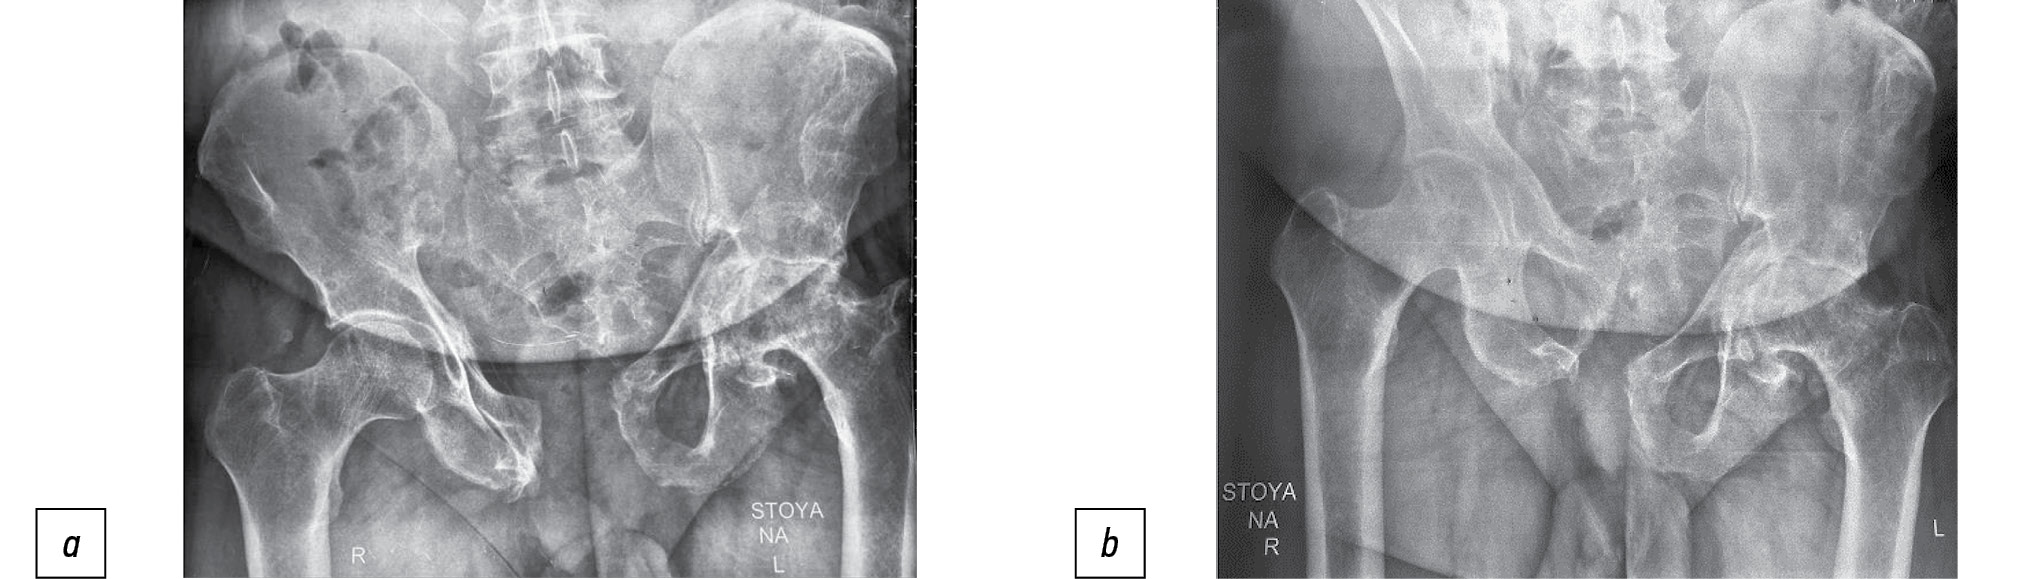

A patient aged 56 years presented 11 months after an injury (fall from the 5th floor). CT showed fractures of the pubis and ischium on both sides, and a longitudinal fracture of the lateral sacral masses on the left side in the Denis 2 area (Fig. 4).

Grade III vertical displacement according to Shlykov classification (45-mm asymmetry of the hip joints) was noted. The patient was on bed rest from the moment of injury, and no verticalization was done. Open repositioning of the left hemipelvis and bilateral PTF were performed. The surgery resulted in a 35-mm displacement and a residual displacement of 10 mm (Fig. 5).

Two weeks later, the patient underwent fixation of the anterior pelvic ring with a reconstructive plate (Fig. 6).

Fig. 6. Fixation of the anterior semicircle of the pelvis with a reconstructive plate: а — intraoperative photo; b — AP-radiography of the pelvis.

On postoperative day 3, the patient started to sit up and within a week stood up with a walker. In the assessment of the long-term treatment results, the quantitative value of the final index according to the Majeed score was 76 points, which corresponds to a good functional result.